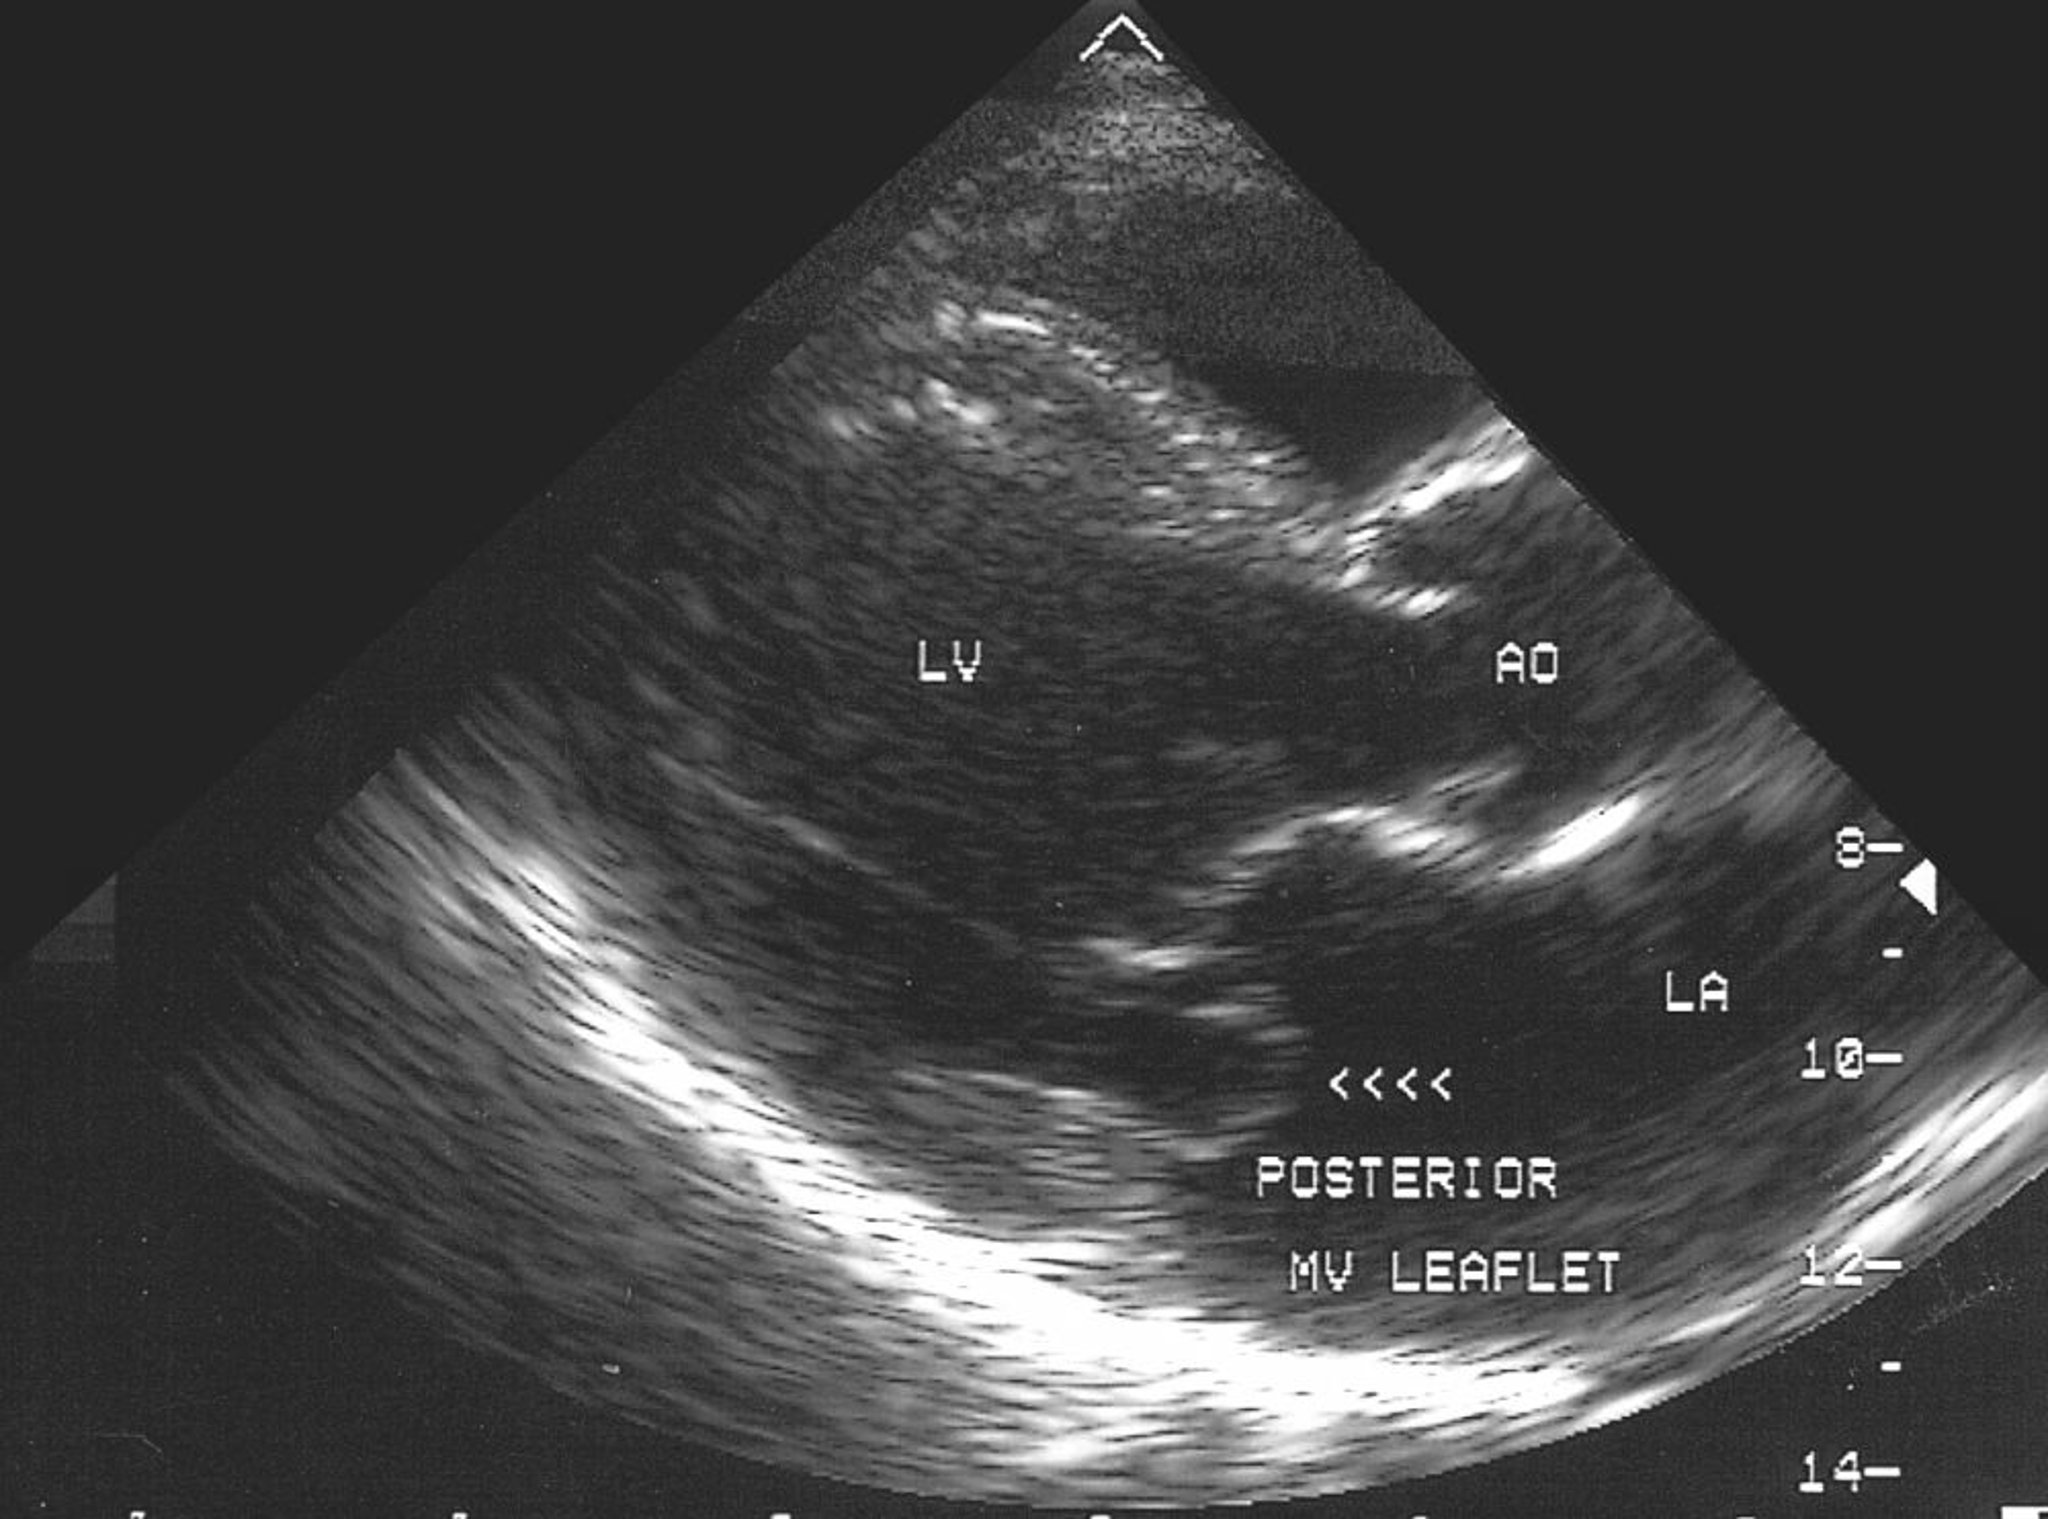

Prolapso de la válvula mitral (ecocardiografía)

Esta imagen ecocardiográfica muestra el prolapso de la valva posterior de la válvula mitral hacia la aurícula izquierda.